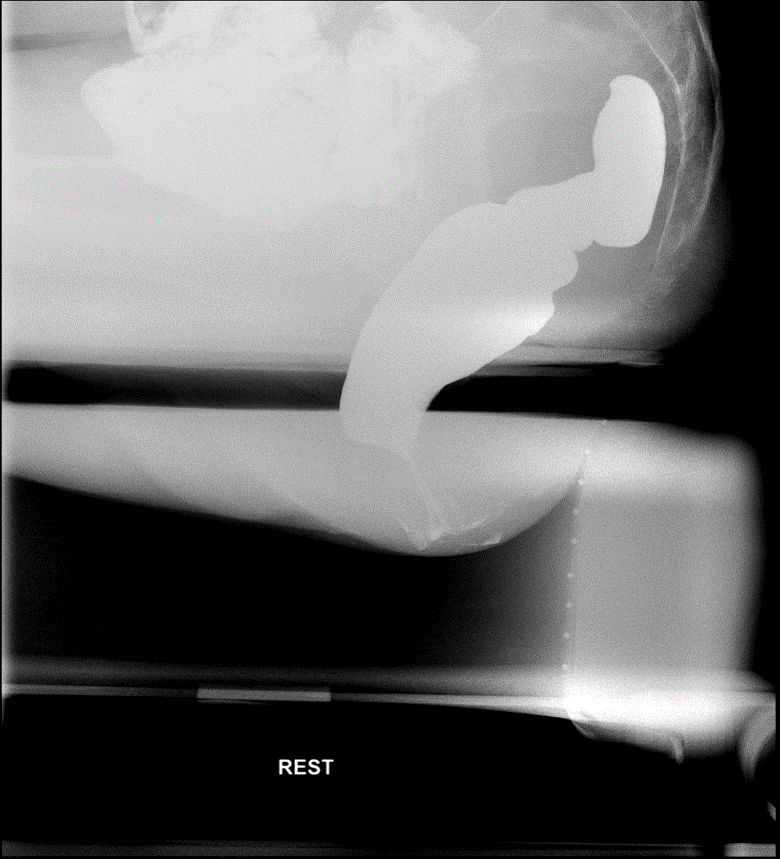

- Obtain spot films while that patient performs the following maneuvers:

- Rest

(key image 2).